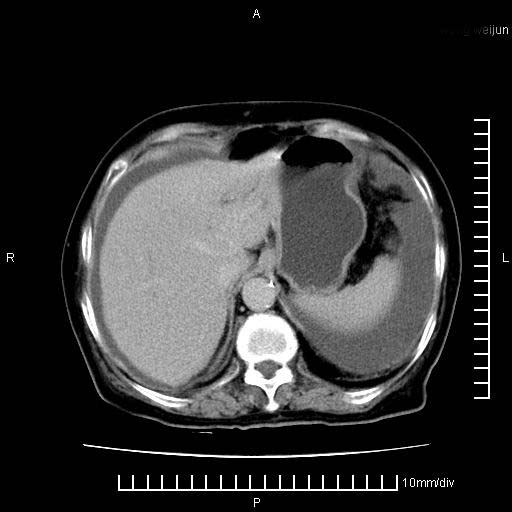

上腹疼痛月余,外院核磁诊断胰腺癌。现临床示右下腹可明显触及包块,可片子上怎么没有看到?

1.胰腺颈体部癌。

胰腺体部癌累及周围器官,腹膜、粘连

1。胰腺ca伴腹膜腔转移

2。肝左叶低密度灶,考虑转移可能

支持胰腺癌肝内转移,腹水改变。

胰腺结构模糊,胰尾部见囊性包块,周围脂肪密度增高,左肾前筋膜增厚,胸水、腹水。不符合胰腺ca伴腹膜腔转移。考虑胰腺炎伴假性囊肿形成、胸腹腔积液。

1、考虑胰腺癌伴腹膜腔转移,胸腹水。

2、肝脏转移可能。

1)考虑胰腺癌并胰腺假性囊肿形成。2)肝内低密度灶,不排除转移。3)右肾盂积水。4)腹水。5)右侧胸腔积液并右肺下叶部分膨胀不全。

考虑胰腺ca伴腹膜腔转移、肝左叶转移、右肾积水。右胸腔积液。